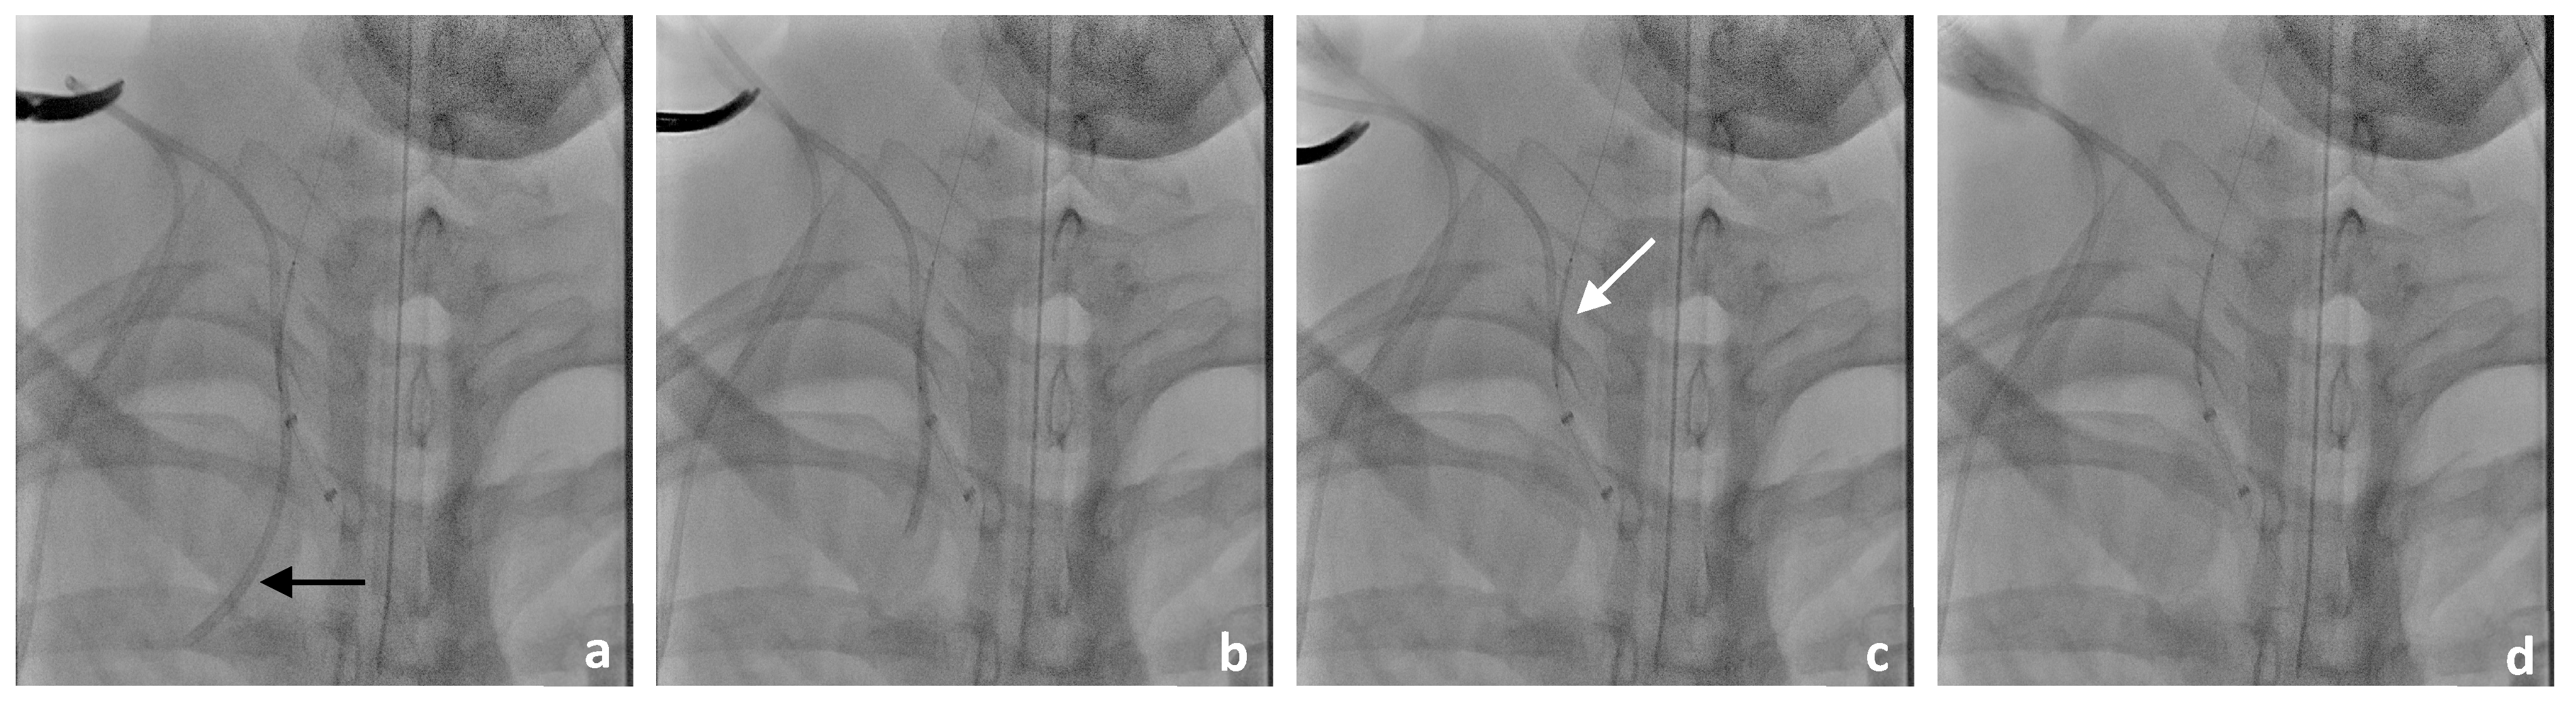

3.2. Neurointerventional Procedure

3.4. Postinterventional Result